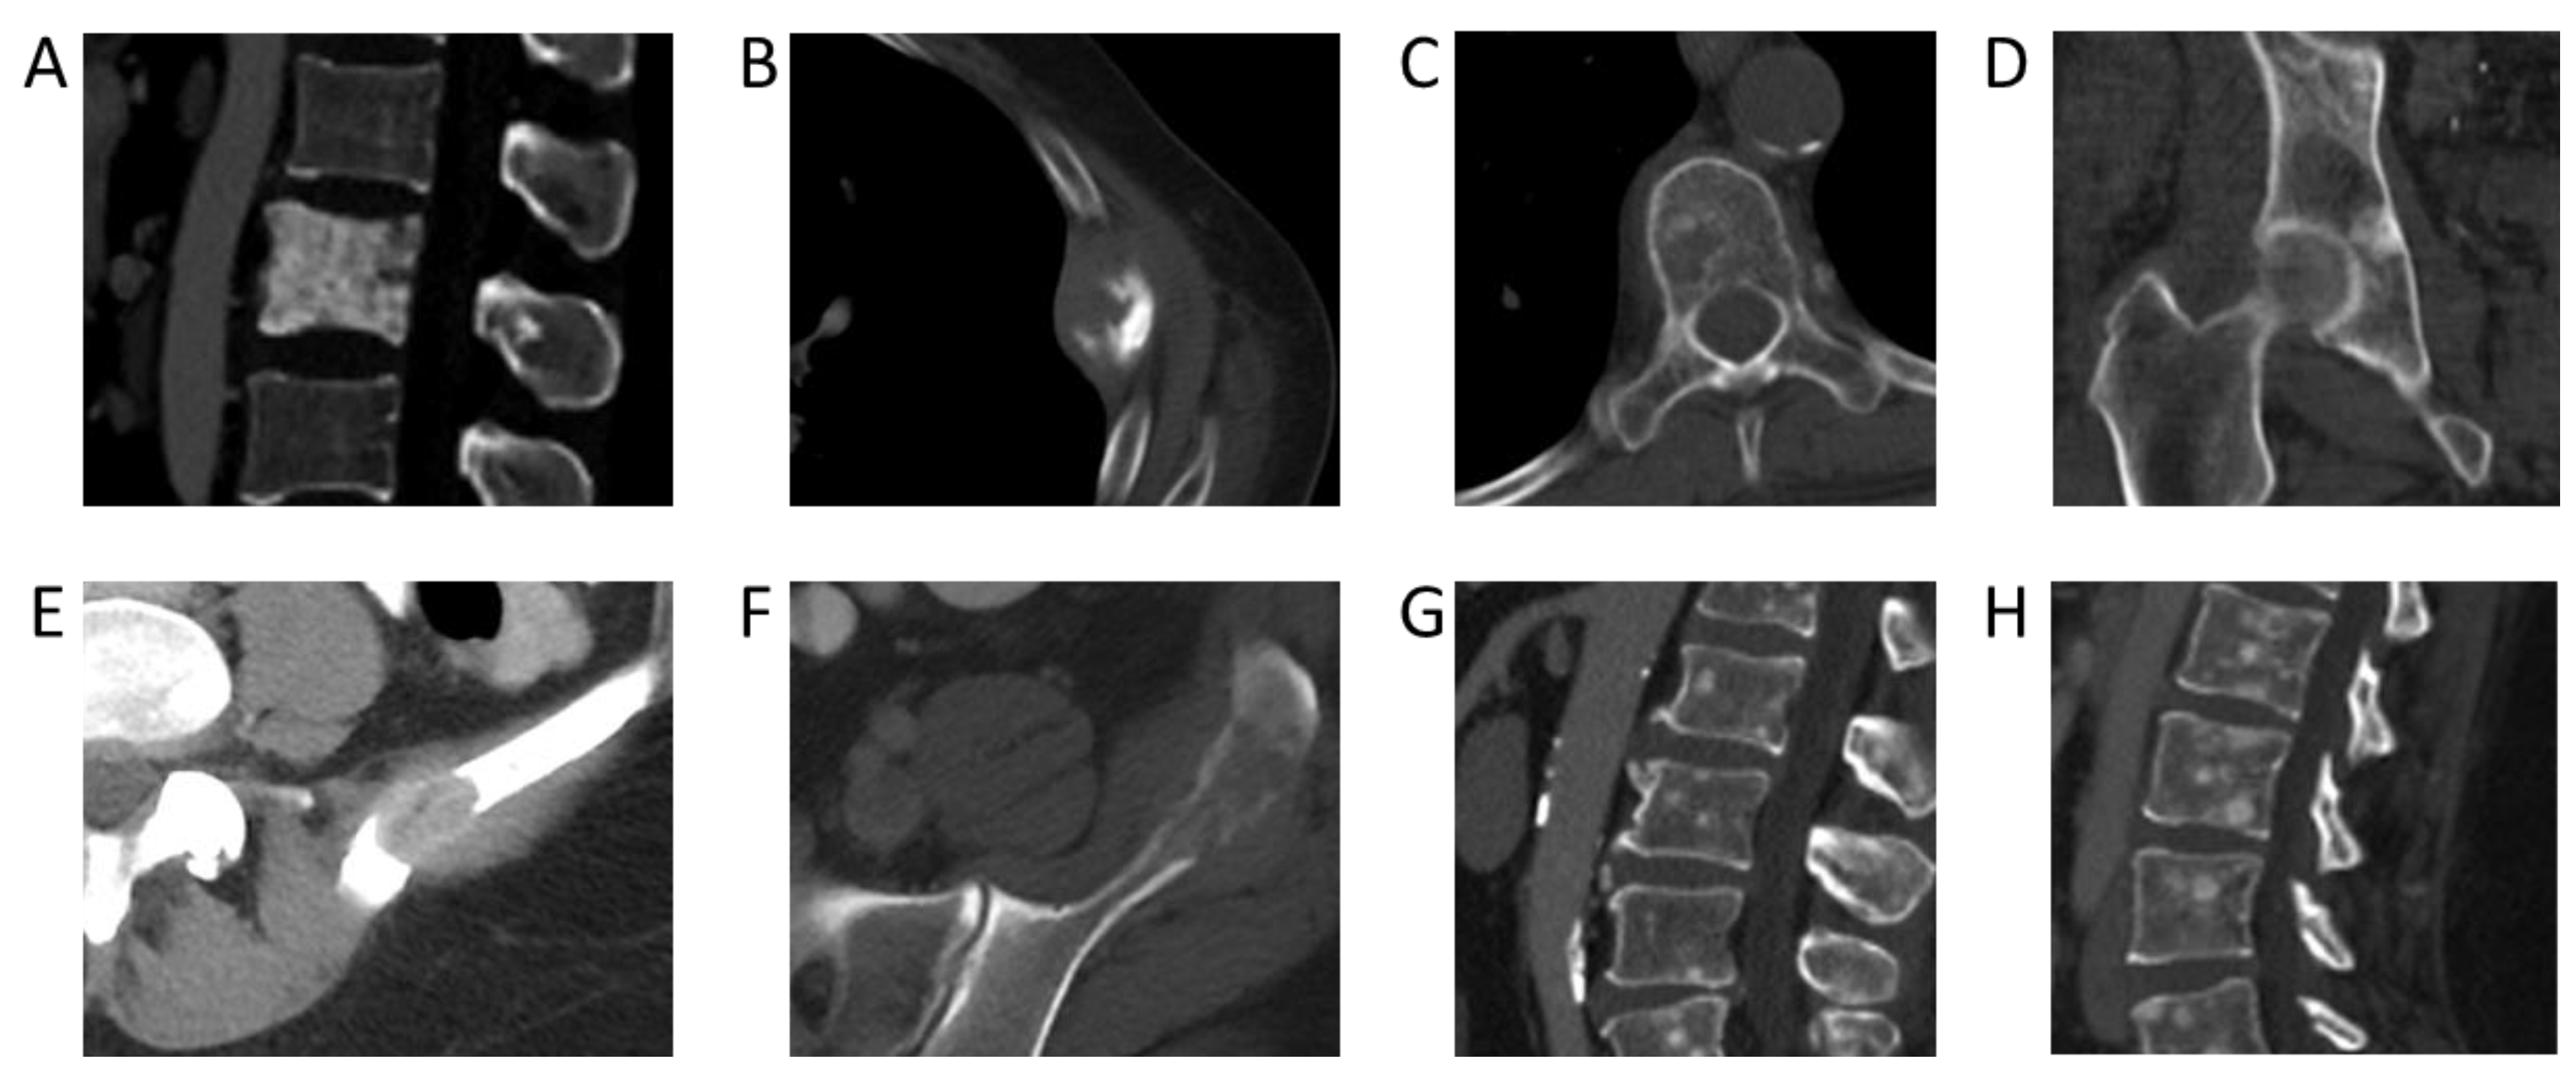

Using the NLP model, the cancer with the highest 5-year incidence rate of bone metastases was prostate cancer, with an incident rate of 52% (95% confidence interval [CI]: 50–54%). This was followed by breast cancer, with an incident rate of 41% (95% CI: 39–42%), head and neck cancer, with an incidence rate of 36% (95% CI: 32–40%), and lung cancer, with an incidence rate of 33% (95% CI: 32–34%) (Table 1). Incidence rates of bone metastases across melanoma, hepatobiliary, pancreatic, and esophageal cancers were also high (from 20–30%). Examples of CT images from cancers with a high incidence rate of bone metastases are shown in Figure 2.

Figure 2. Bone metastases from primary cancers with the highest incidence rates. (A) Sclerotic pelvic metastases in a 76-year-old male patient with prostate cancer. (B) Lytic metastasis in the left third rib in a 60-year-old female patient with breast cancer. (C) Lytic metastasis left pubic bone in a 48-year-old female patient with thyroid cancer. (D) Sclerotic metastasis in an L1 vertebral body in a 59-year-old male patient with adenoid cystic carcinoma of the tongue. (E) Lytic metastases in the left sacral ala and left ilium in a 65-year-old male patient with poorly differentiated lung adenocarcinoma. (F) Multiple sclerotic pelvic bone metastases in a 57-year-old male with a lung carcinoid tumor. (G) Sclerotic right iliac metastasis in a 63-year-old female patient with melanoma. (H) Lytic left sacral metastasis in a 55-year-old female patient with melanoma. (I) Lytic left second rib metastasis in a 60-year-old female patient with hepatocellular carcinoma. (J) Multiple lumbar spine sclerotic metastases in a 92-year-old male patient with hepatocellular carcinoma. (K) Lytic left iliac metastasis in a 67-year-old male patient with esophageal cancer. (L) Follow-up demonstrating interval sclerosis of the left iliac metastasis representing treatment effect.